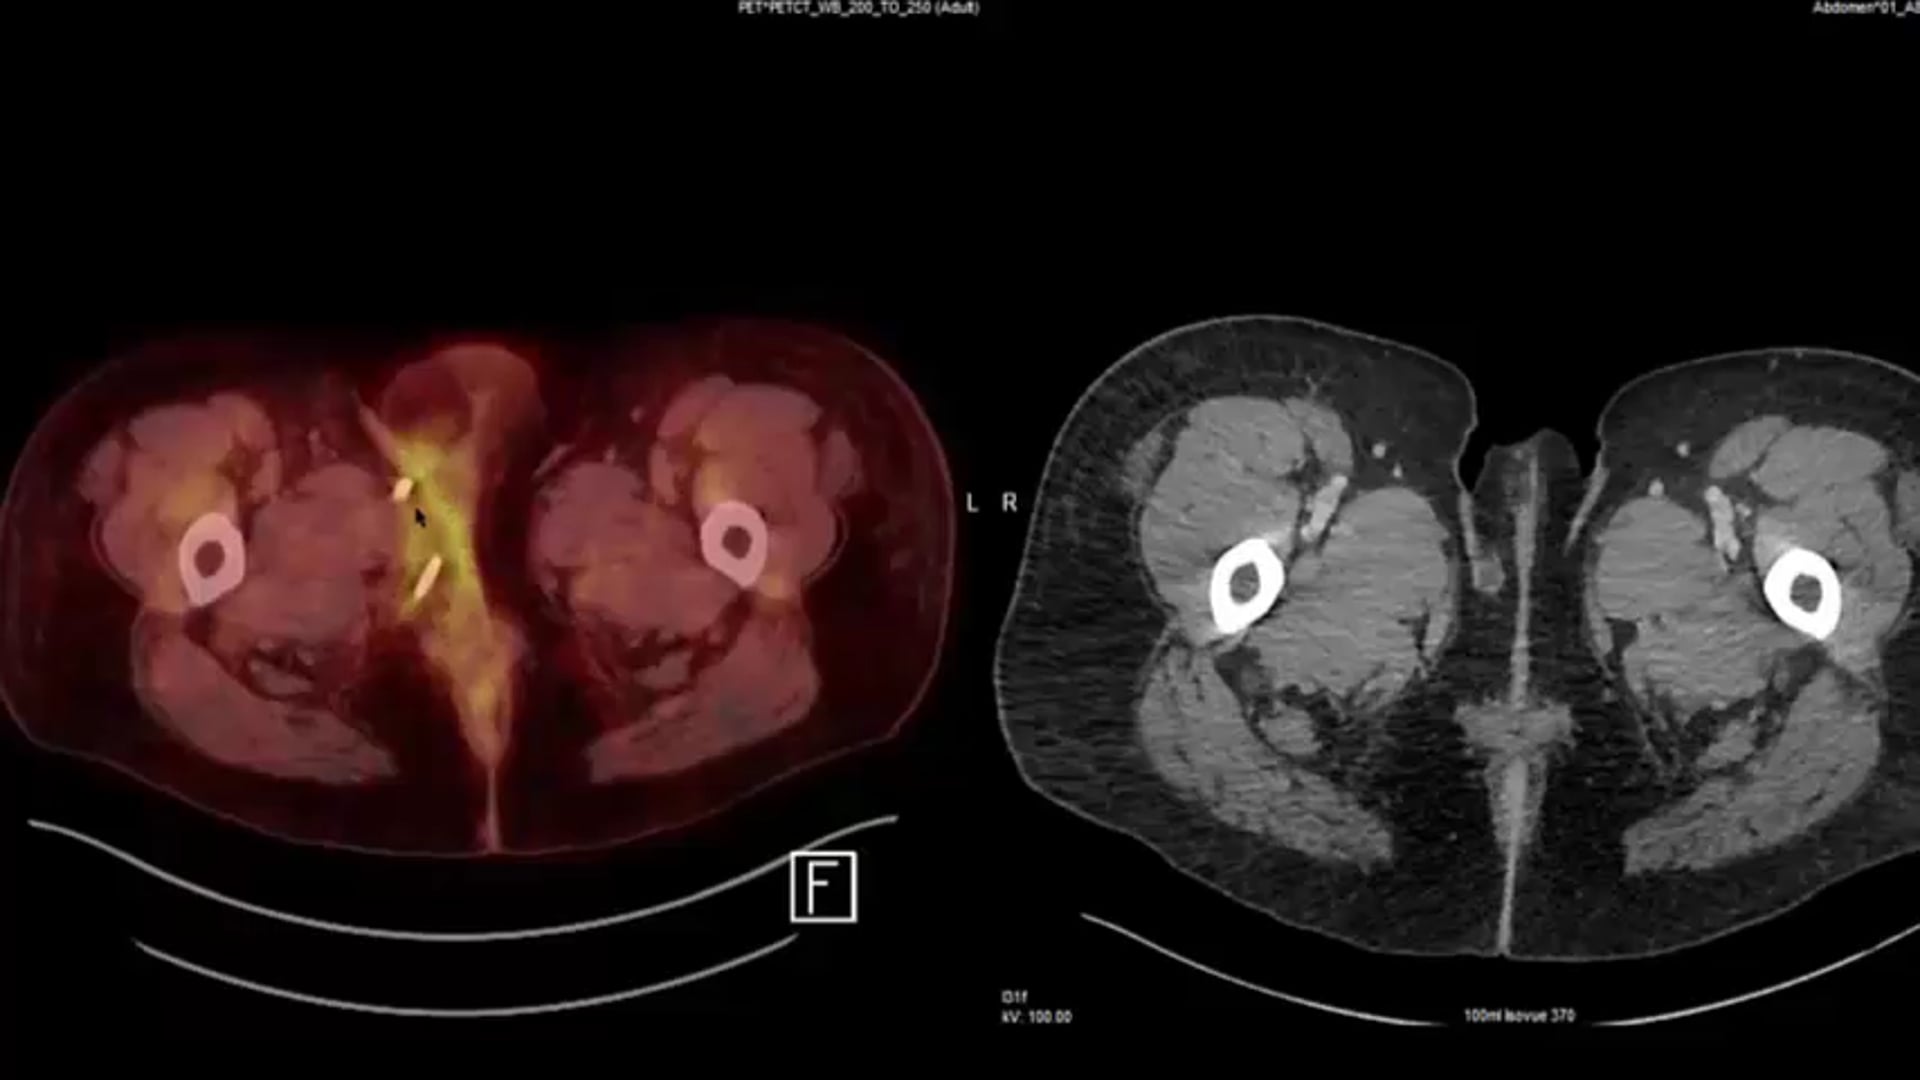

63 yo Anal T3

Large LN adjacent to tumor

Nodes conedown/boost